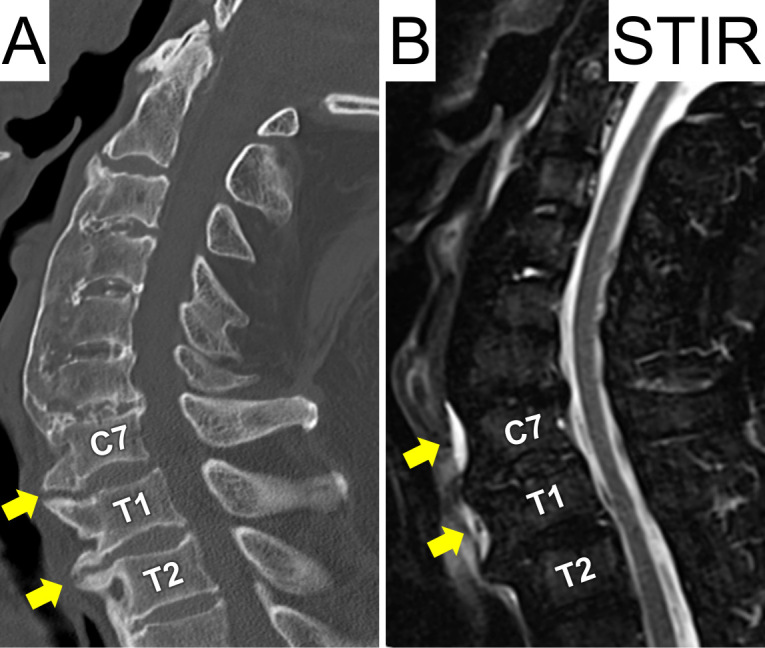

Intramedullary Spinal Cord Abscess due to Traumatic Esophageal Perforation Associated with Cervicothoracic Anterior Osteophytes: A Case Report.